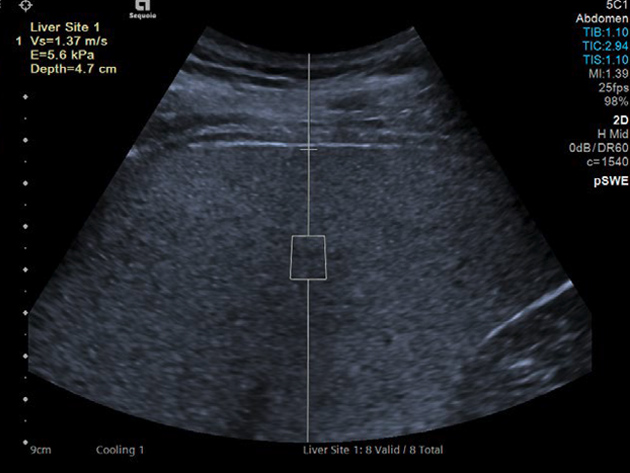

Απεικόνιση 3